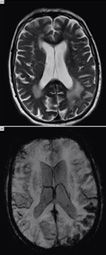

Клинический случай 3: травматическое кровоизлияние

Пациент:

48-летняя женщина направлена в отделение неотложной помощи по поводу рвоты и головной боли; ранее пациентка выписалась после выявления у нее тромбоза вен коркового вещества.

Данные визуализации

При мрт обследовании выявлено несколько двусторонних очагов сниженной интенсивности сигнала в пределах борозд лобной доли и ряд поражений вне вещества мозга. При дополнительном расспросе выяснено, что пациентка недавно перенесла черепно-мозговую травму; наиболее вероятной причиной выявленных изменений были участки кровоизлияния вне вещества мозга и мелкие контузии коркового вещества.